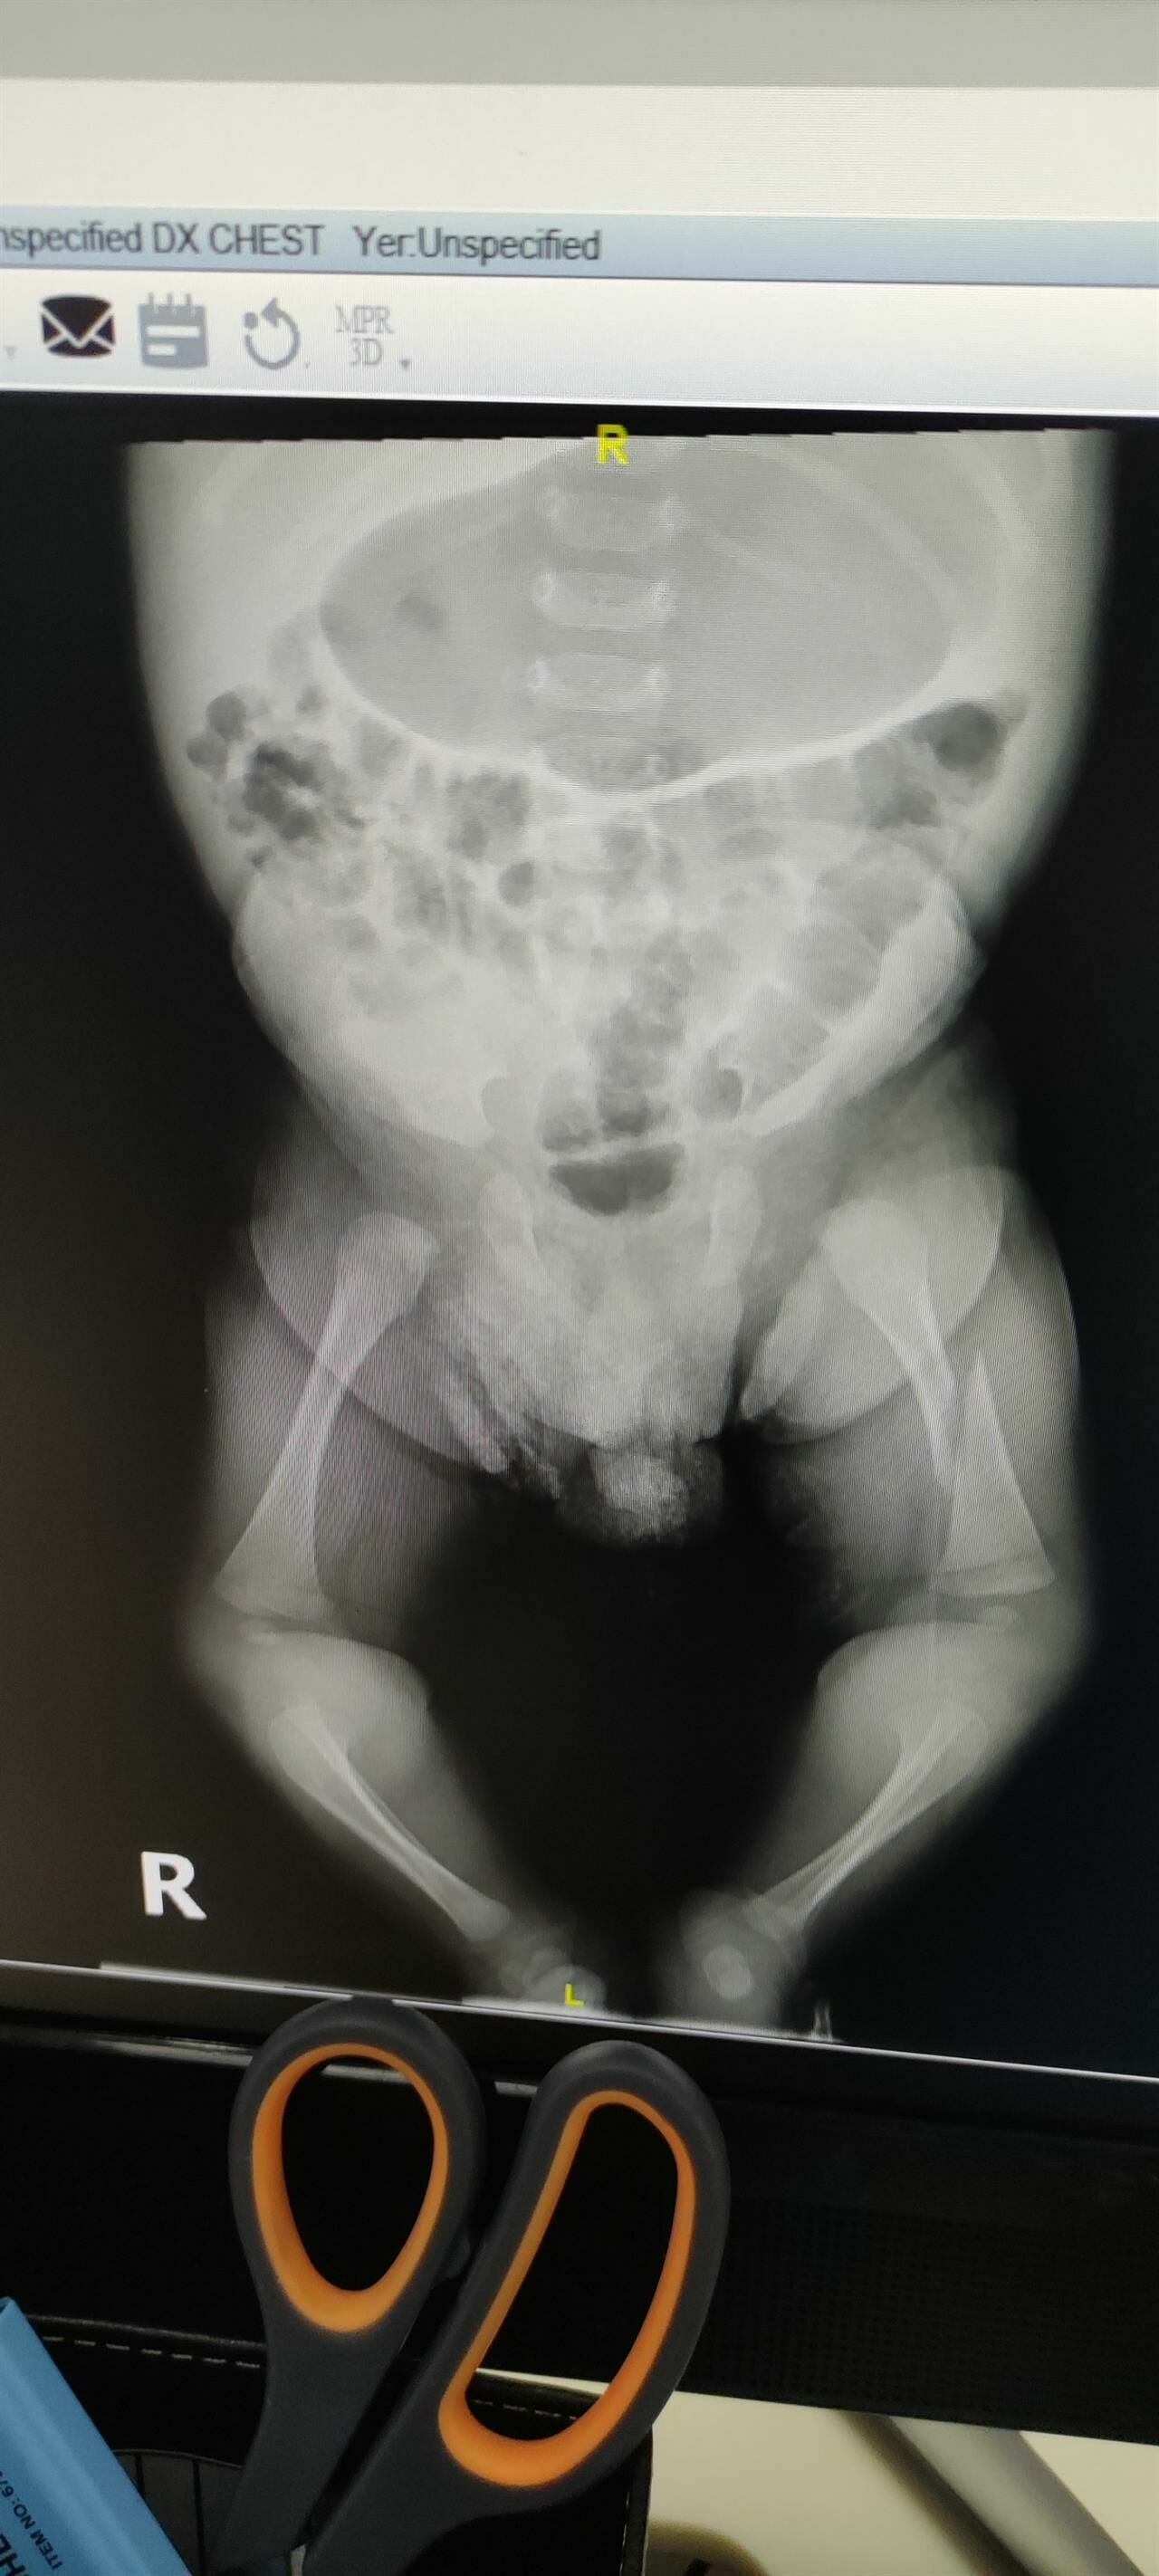

Bebek, idrar yolu enfeksiyonu teşhisi konulduktan sonra özel bir hastanenin yeni doğan yoğun bakım ünitesine yatırıldı. Bir hafta süren tedavi sonrasında aileye, bebeğin bacağının kırıldığı bilgisi verildi. Hastane yetkilileri, bebeğin kendi kendine dönerken bacağını kırdığını iddia etti.

Hastane, epikriz raporunda çocuğun bacağının hastanede kırıldığını kabul etti. Ancak, Sağlık Bakanlığı’nın konu hakkında daha fazla bilgi vermesi bekleniyor. Aile, hastanenin ve Sağlık Bakanlığı’nın konu hakkında daha fazla açıklama yapmasını talep ediyor.